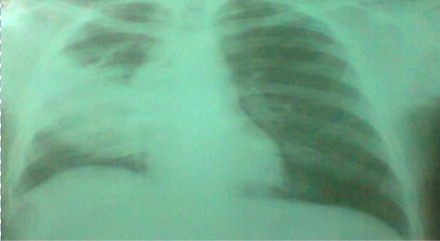

Rayos X de tórax: se pudo apreciar radiopacidad del lóbulo medio

(Figura 1).